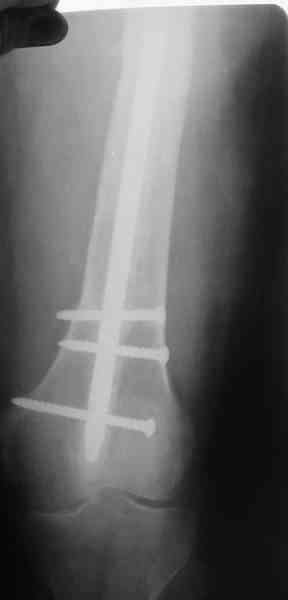

В качестве демонстрации лечения канального остеомиелита бедренной кости представляем пациентку (см. parts 2 и 3), которая как раз сегодня была у нас на контрольном осмотре. В мае этого года мы произвели ей фиксацию бедренной кости штифтом-спейсером по поводу ложного сустава и канального остеомиелита бедренной кости. Через 4 недели после операции свищи закрылись. Сейчас она ходит с полной нагрузкой на конечность.

4, 5, 6 - рентгенограммы бедра и фотографии пациентки (прошу прощения за низкое качество рентгеновских снимков) от 7 сентября 2007 г.